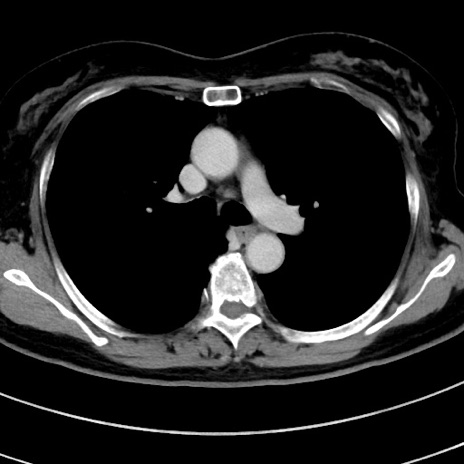

症例9(横断像)

【症例】 60歳代女性

【主訴】むかつき、みぞおちの痛み

【現病歴】3日前よりむかつきがあり、食事がとれない。

【既往歴】糖尿病

【身体所見】発熱なし、心窩部圧痛軽度あるも、腹膜刺激症状なし。

【データ】WBC 7400、CRP 1.92